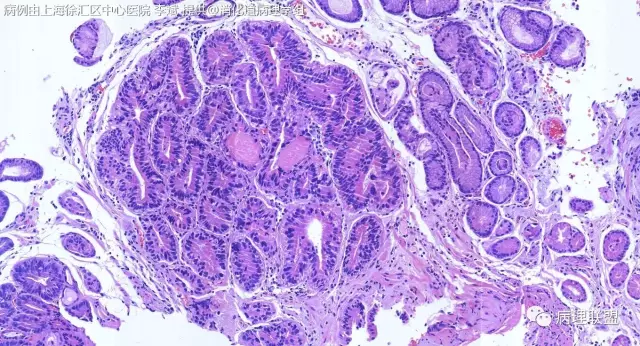

F-56 胃窦粘膜活检(低级别 vs 高级别)

女,56岁,胃窦粘膜活检(病例由上海徐汇区中心医院 李斌 提供,致谢!)

考虑:低级别上皮内病变(轻度异型增生)。

@李斌,高级别,腺体结构乱复杂,核异型性大,极向乱

@左淑英 子宫内膜受激素周期影响,腺体结构和上皮变化比较大,消化道受损伤、炎症等影响比较大,同样要看结构、看细胞,但标准确实不大一样。虽然具体病例需要具体分析,但我感觉在胃肠道,对于判断时感觉模棱两可的病例,表面成熟现象是区分反应性增生和低级别异型时可重复性相对比较好的指标;核极向是区分高低级别异型增生时可重复性相对比较好的指标。供参考